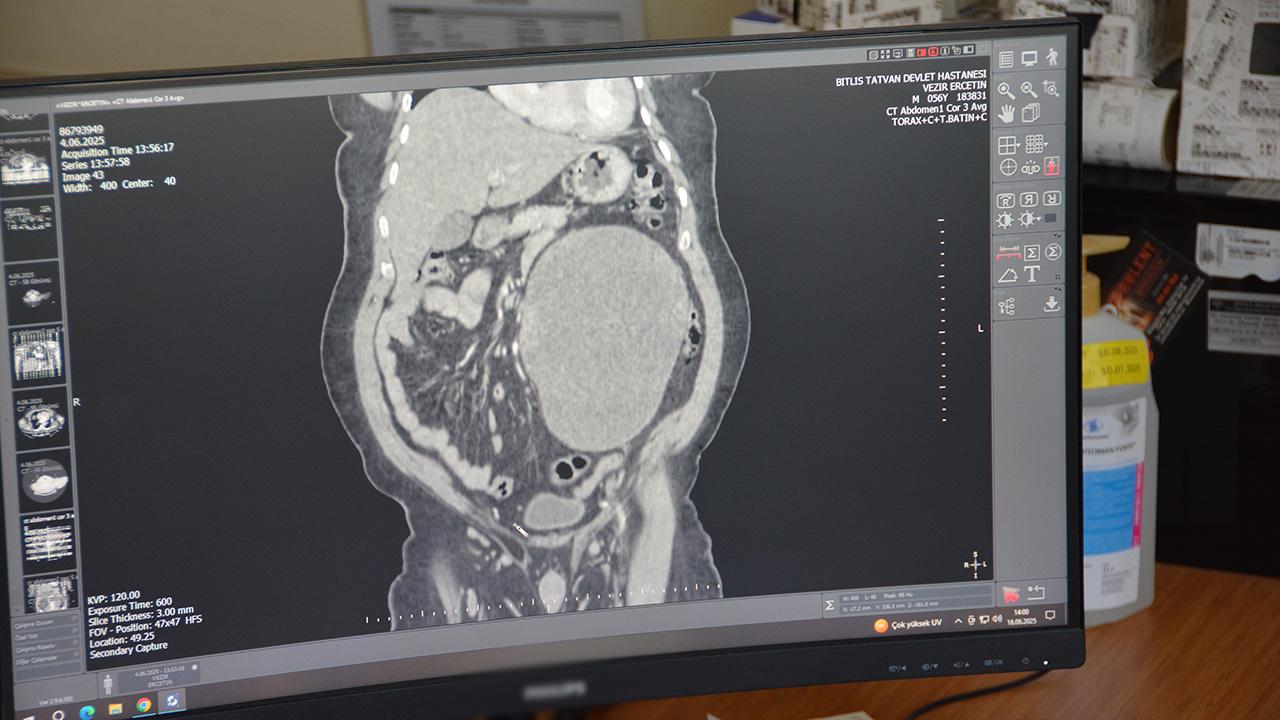

Bitlis’in Adilcevaz ilçesinde yaşayan 56 yaşındaki Vezir Erçetin, karın ağrısı ve şişlik şikayetiyle Tatvan Devlet Hastanesi’ne başvurdu. Yapılan tomografi ve ultrason incelemelerinde sol böbreğinde yaklaşık 23 santimetre çapında büyük bir kist tespit edildi.

Üroloji uzmanı Operatör Dr. Ercan Bayrak’ın yaptığı açıklamaya göre, bu boyutta bir kistin nadir görüldüğü ancak çevre organlara baskı yaptığı için karın ağrısı ve şişlik şikayetlerine yol açtığı belirtildi. Acilen hazırlık yapılan cerrahide kist, böbrek dokusuna zarar vermeden tamamen alındı. Operasyon sonrası sol böbreğin idrar toplama sistemi korunarak normal işlevine geri kavuşturuldu.